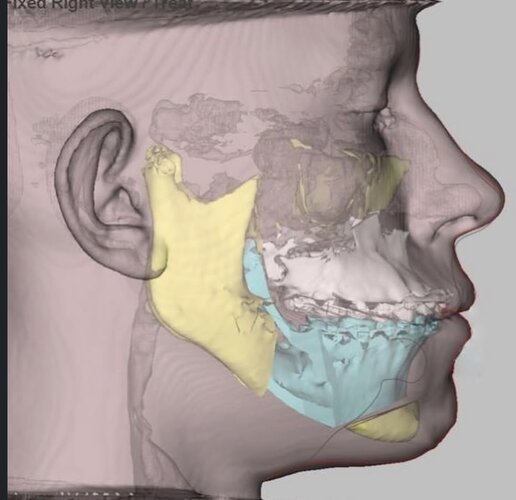

Fucking insane this is anatomically possible lol. Looks good though.

3 whole centimetres on the lower jaw is insane, maybe it’s not over for some of you. Just gotta find a surgeon willing to do such movements.

The amount of upper jaw movement is unclear from what the surgeon has said, but it isn’t massive as seen by the scans and the fact that the patient’s upper lip has not been chimpified.